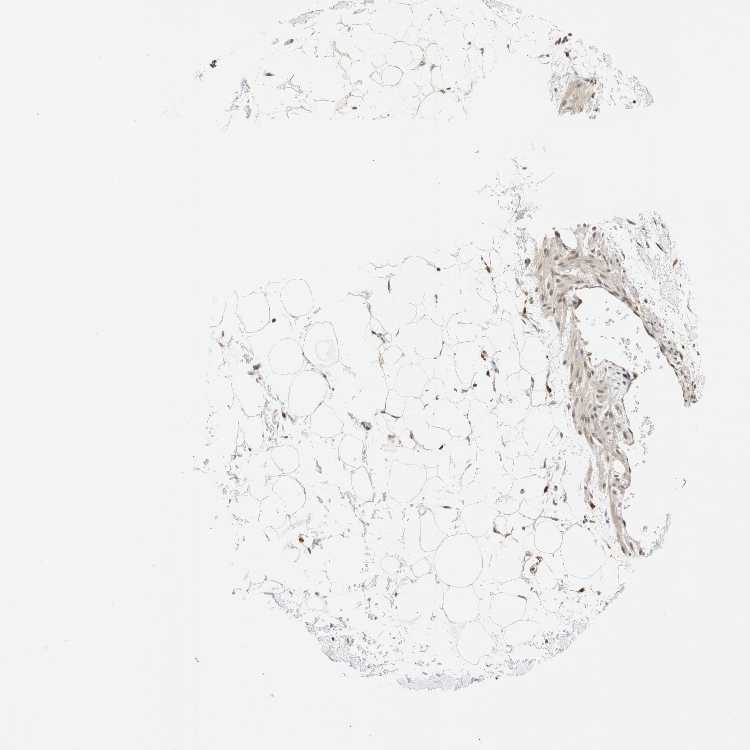

ADIPOSE TISSUE - Antibody stainingi

Antibody staining in the annotated cell types in the current human tissue is reported as not detected, low, medium, or high, based on conventional immunohistochemistry profiling in selected tissues. This score is based on the combination of the staining intensity and fraction of stained cells.

Each image is clickable and will lead to virtual microscopy that enables deeper exploration of all samples and also displays staining intensity scores, fraction scores and subcellular localization as well as patient and tissue information for each sample.

Antibody HPA007674

Adipocytes Medium